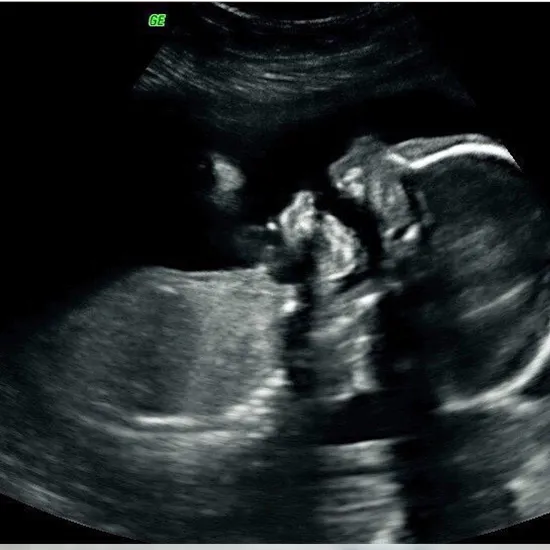

A fetal biophysical manning, also known as Biophysical profile or simply BPP, is a prenatal test used to assess baby's health. The test uses ultrasound and NST to evaluate Fetal heart rate, Fetal movements, Fetal breathing, Fetal tone, and amniotic fluid volume. A scoring system is used and the score is termed as Manning’s score. Each parameter is given a minimum score of 0 and a maximum score of 2, and the maximum total score is 10. Fetal acidemia is declared when the total score is 4 or <4.

1. Ultrasound: You will be asked to lie on the examination table. Your sonographer will apply gel over your abdomen and a transducer/probe will be moved over the abdomen which sends high frequency sound waves to the body parts. These sound waves are reflected back and are recorded by the ultrasound machine and converted into images or graphs. These images will be interpreted by your sonographer to assess your condition.